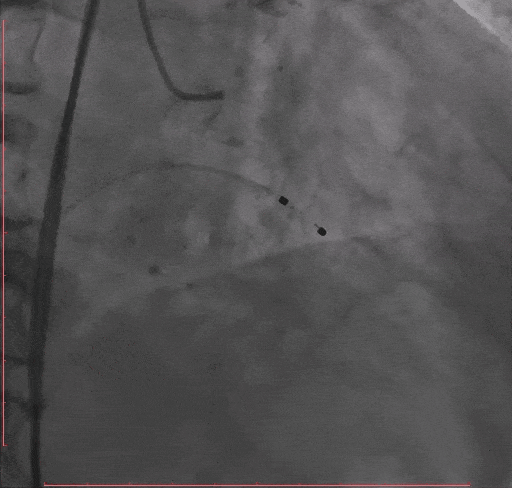

Step 2.冠脉造影

Step 3.导丝跨主动脉瓣后,干预冠脉病变,球囊无法通过LAD病变,予以旋磨